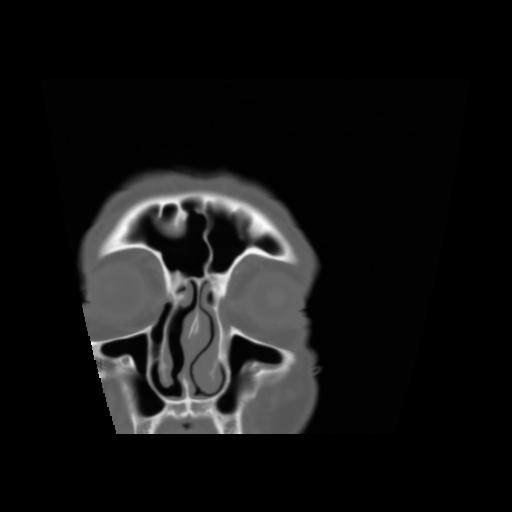

5 CEREBRO,,Coronal,3.000,CEREBRO,Coronal,